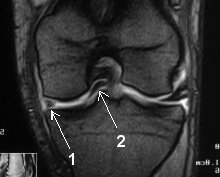

Un patient s’est présenté aux urgence pour blocage aigu du genou, une IRM est réalisée que voit-on?

Anse de seau luxée dans l’échancrure intercondylienne